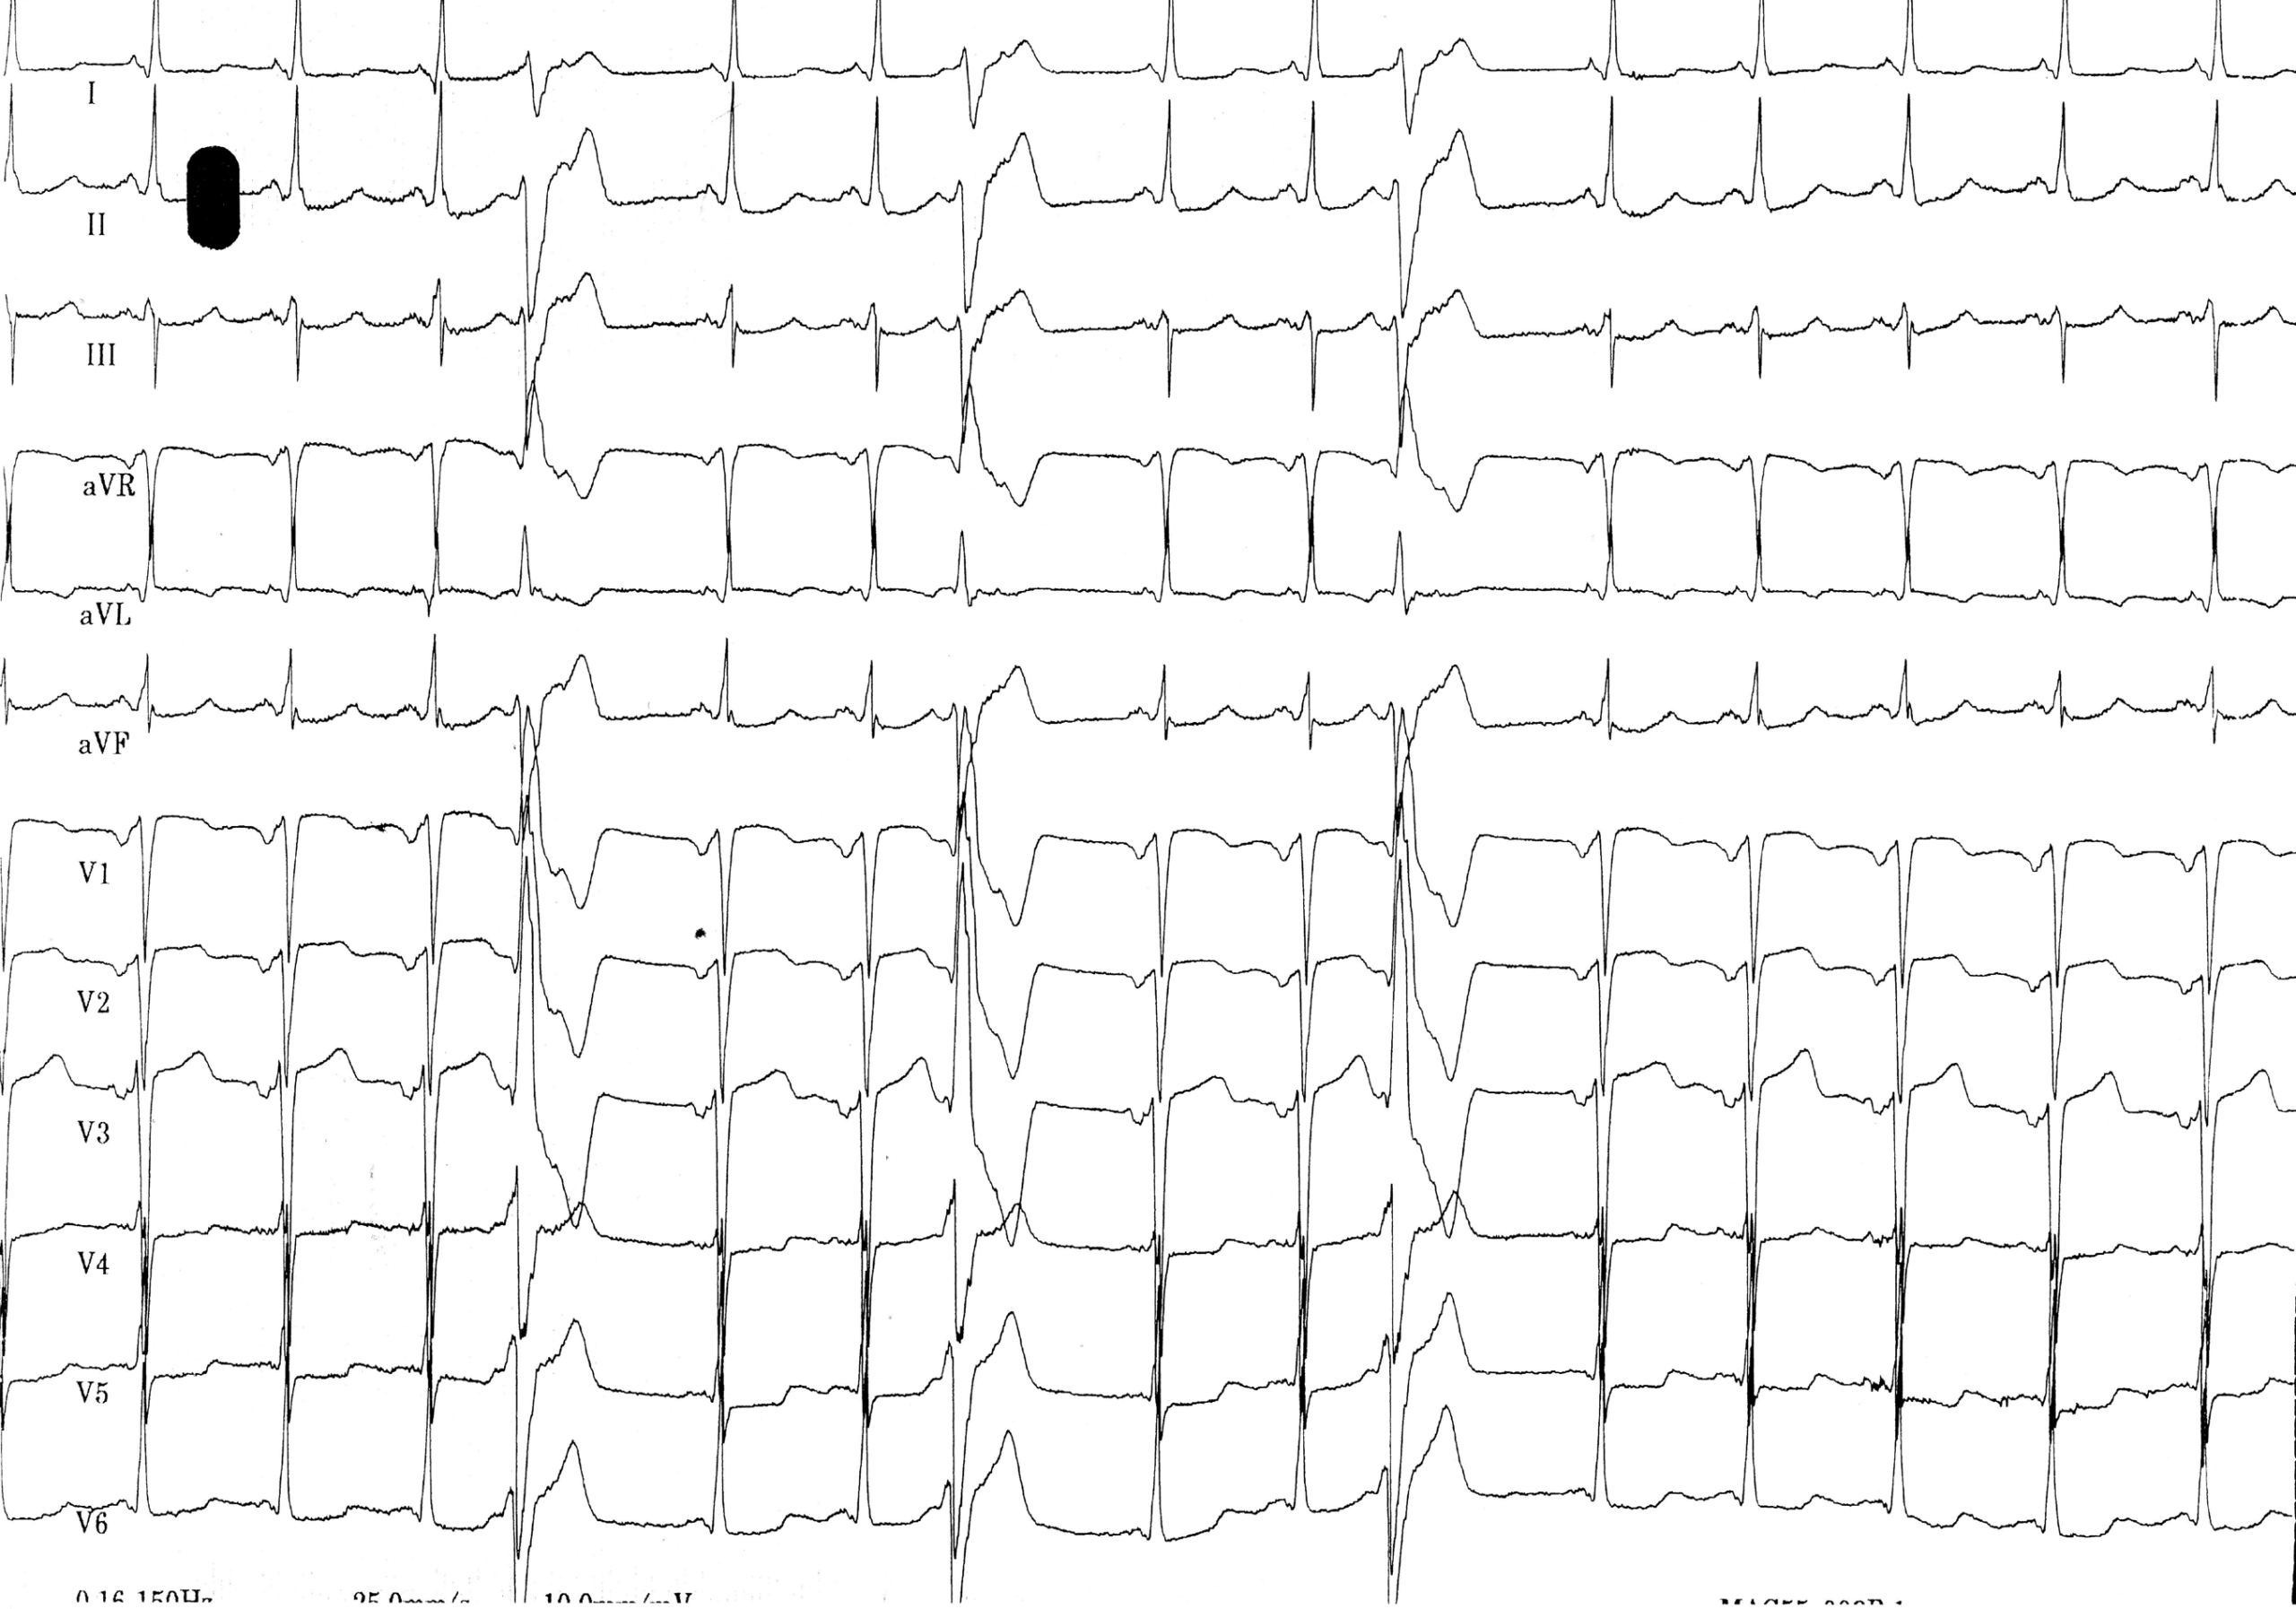

Sur l’électrocardiogramme, une extrasystole ventriculaire se caractérise par l’existence d’un QRS prématuré, ectopique, à QRS large (> 120 ms), sans association avec une activité atriale précédente. Les extrasystoles ventriculaires doivent plus être considérées comme un marqueur de risque qui doit orienter vers la recherche d’une cardiopathie et non comme un facteur de risque indépendant sur lequel il faut agir. La recherche d’une cardiopathie causale est donc un temps essentiel de la prise en charge.

Chez ce patient: 1) l’analyse du QRS conduit sur activité sinusale est très en faveur de l’existence d’une cardiopathie ischémique. On retrouve en effet, des signes d’hypertrophie auriculaire gauche mais également des signes de séquelle de nécrose antérieure confirmés par l’anamnèse et l’analyse des antécédents du patient. 2) la morphologie des extrasystoles est également en faveur de l’existence d’une cardiopathie. La largeur des complexes QRS ectopiques est importante et dépasse les 180 ms ce qui est évocateur d’une cardiopathie, les extrasystoles bénignes survenant sur coeur sain étant généralement plus fines (de l’ordre de 140 ms). Les extrasystoles ont un aspect crocheté, polyphasique et une amplitude relativement faible, autant d’arguments en défaveur d’un caractère bénin. La fragmentation des extrasystoles est considéré comme un facteur péjoratif car traduisant une propagation de l’influx électrique à travers un myocarde ventriculaire aux propriétés de conduction altérées, dans un myocarde cicatriciel ou fibrosé. Chez les patients avec myocardiopathie ischémique, le retard et l’axe des extrasystoles sont souvent dictés par la localisation de la séquelle de nécrose puisque ces extrasystoles sont soit le reflet d’une activité normale de cellules au fonctionnement altéré par l’ischémie, soit le résultat d’une réentrée autour de circuits à propagation lente de l’influx électrique dans les zones cicatricielles.